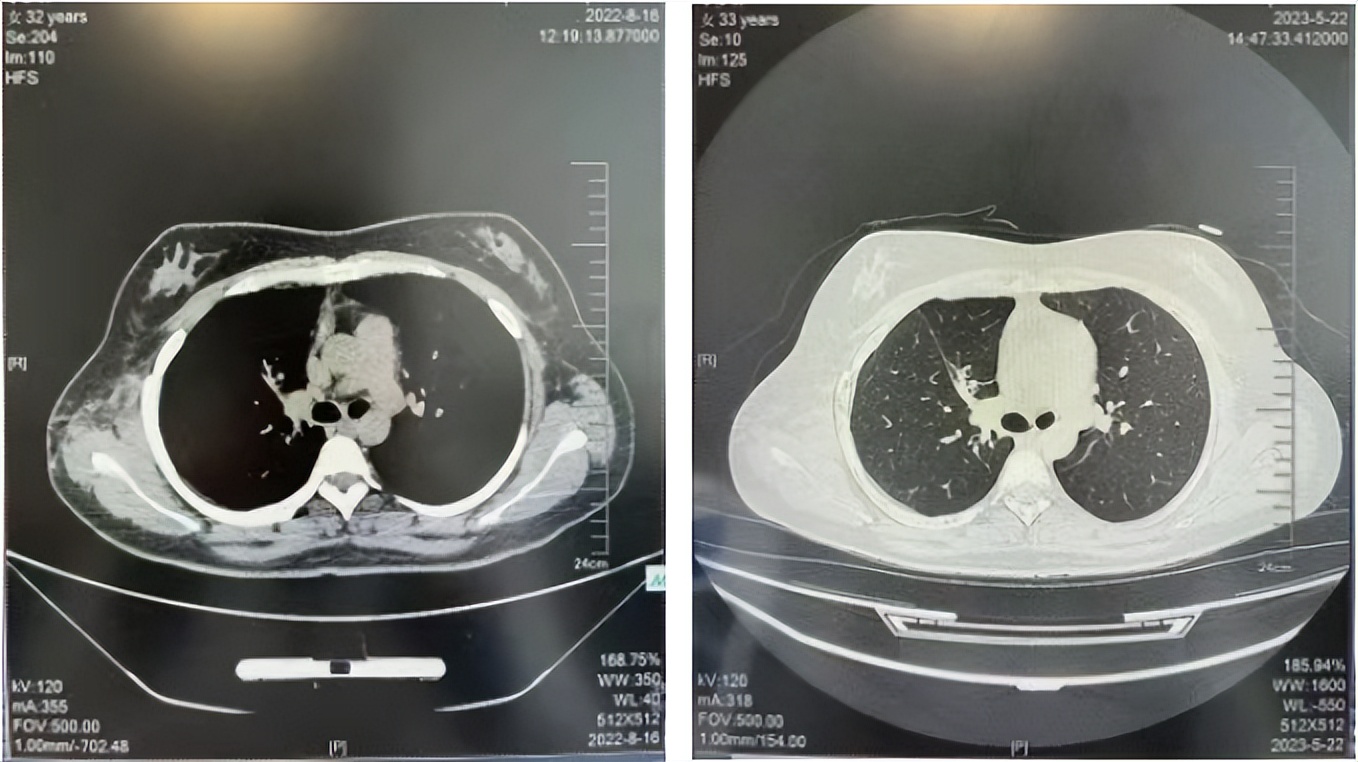

2016年1月复查CT提示支气管截断可见新发小结节,一线治疗采用培美曲塞+DDP方案化疗4周期(培美曲塞3.36,DDP 480mg)。化疗后复查胸部CT:右肺见不规则结节样影,最大层面大小约19mm*8mm,较前比较明显增大,疗效评估PD。2017.3-2017.4予单药多西他赛化疗3周期,疗效评估SD。2018年5月末复查CT提示结节较前增大,评效为PD,2018年6-10月予多西他赛+CBP化疗4周期,疗效评估SD。2022年5月患者出现活动后气短,复查胸部CT示右肺膨胀不良;右侧胸腔积液增多。胸腔积液包埋病理示符合肺腺癌细胞。行NGS基因检测:EML4:exon13-ALK:exon20融合。PD-L1(克隆号22C3)TPS<1%。

诊疗经过:2022年5月始口服克唑替尼3个月,出现肝功能异常(DILI 2级伴临床症状),改用恩沙替尼靶向治疗至今,目前评效为维持PR。恩沙替尼应用期间出现轻度肝功能异常(DILI 1级),对症处理后好转。截止目前PFS 33个月。

2022.08

2023.05